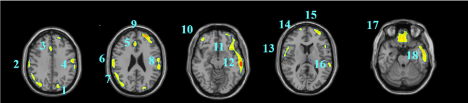

Figure 1A.  Transverse slices showing the deficits of autistics subjects when compared to healthy controls using SPM (p < 0.001 FDR Correction):  1) Occipital Superior Left; 2) Post Central Right; 3) Cingulum Anterior Right; 4) Precentral Left; 5) Cingulum Mid Right; 6) Temporal Mid Right; 7) Angular Superior Right; 8) Temporal Superior Left; 9) Frontal  Superior Left; 10) Frontal Inferior Triangularis Right; 11) Frontal Superior Orbital Left;  12) Temporal Mid Left;  13) Rolandic Operculum Right; 14) Frontal Inferior Right; 15) Frontal Inferior Left; 16) Temporal  Mid Left; 17) Frontal Inferior Orbital Left; 18) Temporal Inferior Left.